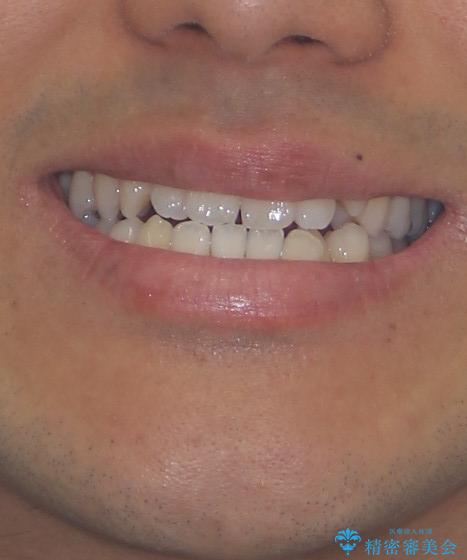

歯列弓の拡大により約1年で矯正治療を終えることができました。

正中も合わせることができ、非常にきれいに仕上がりました。